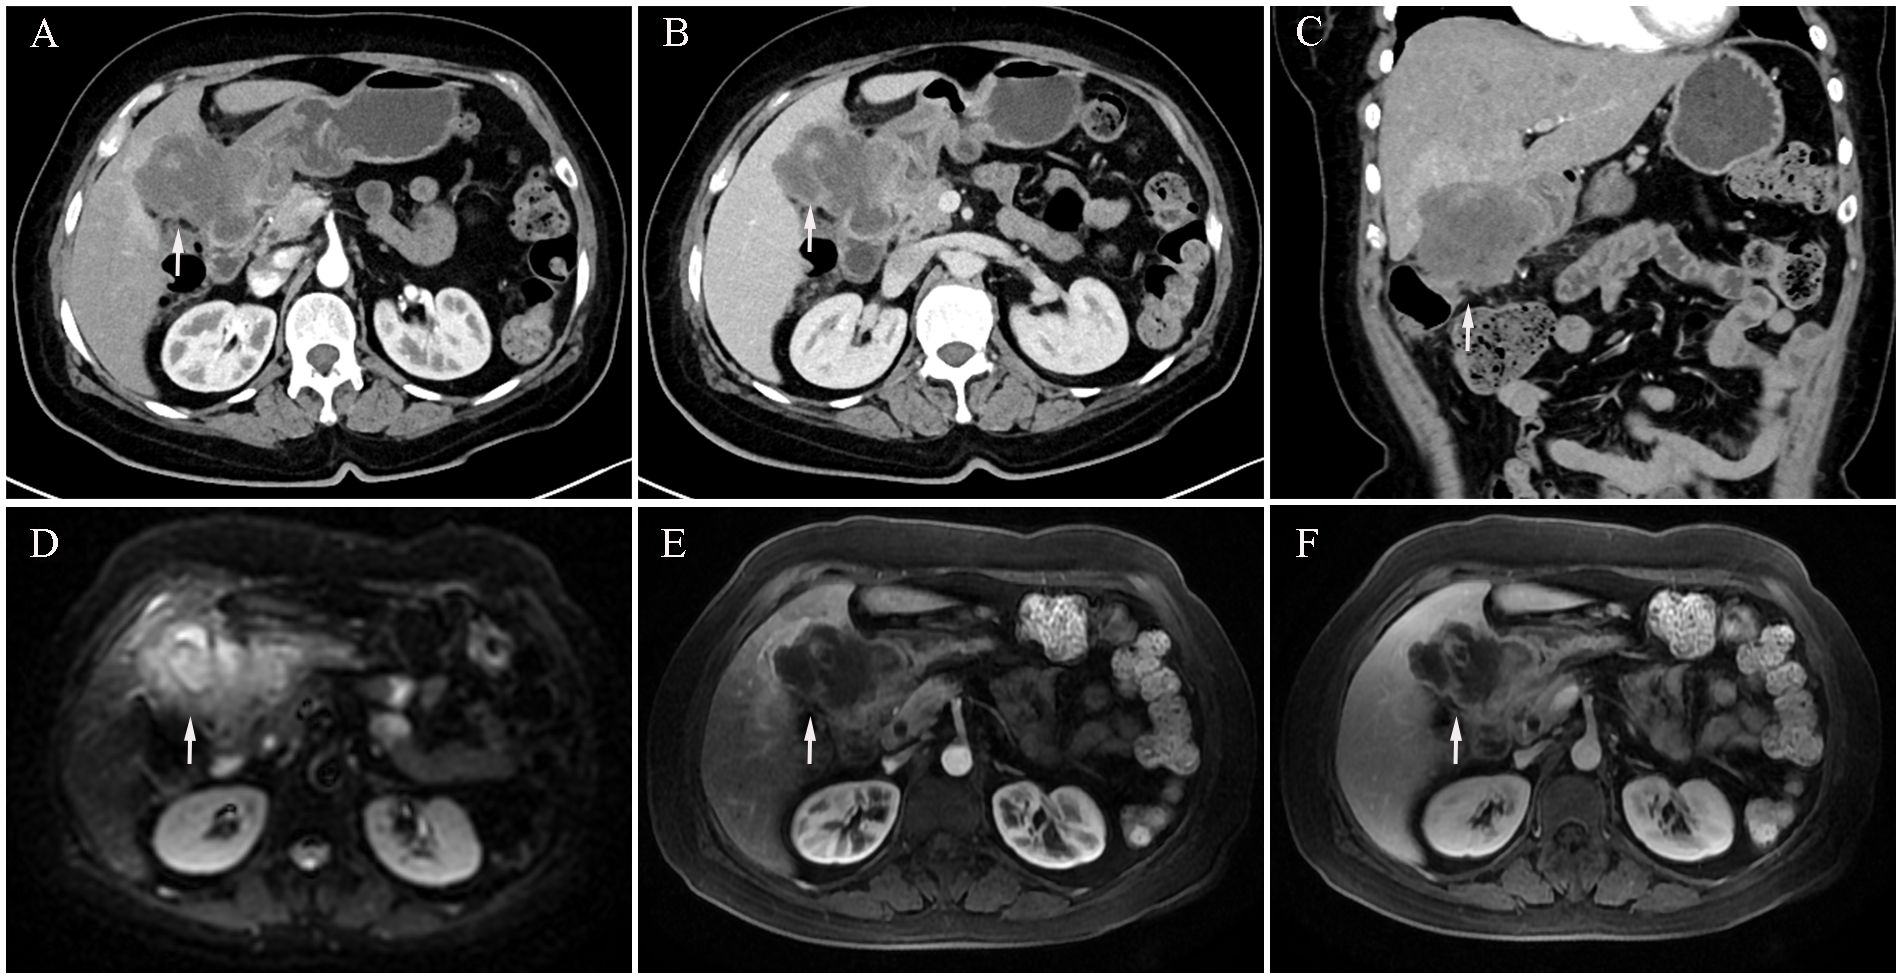

We report the case of a 59-year-old woman who presented with a two-month history of intermittent right upper quadrant pain that was mild, self-limiting, and typically resolved within a few hours. She was admitted to Shulan (Hangzhou) Hospital on March 25, 2020. She denied associated symptoms such as fever, nausea, vomiting, or diarrhea, and had no notable past medical history. On admission, physical examination revealed a firm mass approximately 3 cm in size palpable beneath the right costal margin, corresponding to the liver edge, with mild tenderness elicited on palpation. Laboratory evaluation revealed a mildly elevated white blood cell count of 11.1×109/L (reference range: 3.5–9.5×109/L), a C-reactive protein level of 44.5 mg/L (normal ≤10 mg/L), and a platelet count of 372×109/L (reference range: 125–350×109/L). Fecal occult blood testing returned a positive result. Serum tumor markers were markedly elevated, including carcinoembryonic antigen (CEA) at 24.5 ng/mL, carbohydrate antigen (CA)19–9 at 48.7 U/mL, cytokeratin 19 fragment (CYFRA 21-1) at 9.2 ng/mL, CA72–4 at 8.4 IU/mL, and CA125 at 113.5 U/mL. Contrast-enhanced abdominal computed tomography (CT) revealed an ill-defined, irregular hypodense mass in the gallbladder fossa measuring approximately 7.3 × 6.4 cm, with heterogeneous gallbladder wall thickening and marked, uneven enhancement (Figures 1A–C). The lesion involved adjacent hepatic tissue, the gastric antrum, and the hepatic flexure of the colon, with indistinct margins near the greater omentum (Figures 1A–C). Upper abdominal dynamic contrast enhanced magnetic resonance imaging (MRI) showed the mass as slightly hyperintense on T1-weighted images, heterogeneously hyperintense on T2, and exhibited mixed high signal intensity on diffusion weighted imaging (DWI) (Figures 1D–F). Gastrointestinal endoscopy further confirmed malignant invasion of the descending duodenum and transverse colon (Supplementary Figures S1A, B). Biopsy specimens were obtained, and histopathological analysis confirmed adenosquamous carcinoma (Supplementary Figure S1C). According to the TNM classification system of the American Joint Committee on Cancer (AJCC), a definitive diagnosis of primary gallbladder carcinoma (T4N1M0, Stage IVA) was established based on the clinical and pathological findings.

Figure 1. Initial contrast-enhanced abdominal computed tomography (CT) and Upper abdominal dynamic contrast enhanced magnetic resonance imaging (MRI) at diagnosis (March 25, 2020). (A) CT arterial phase showing marked heterogeneous enhancement of the gallbladder lesion (white arrow, longest diameter was 73 mm). (B) CT venous phase showing marked heterogeneous enhancement of the gallbladder lesion (white arrow). (C) Coronal CT image showing gallbladder lesion invading adjacent liver tissue, gastric antrum, and hepatic flexure of the colon (white arrow). (D) MRI diffusion weighted imaging (DWI) sequence shows mixed high signal intensity with poorly defined tumor margins (white arrow). (E) MRI arterial sequence shows marked heterogeneous enhancement of the gallbladder lesion (white arrow). (F) MRI venous sequence showing marked heterogeneous enhancement of the gallbladder lesion (white arrow).